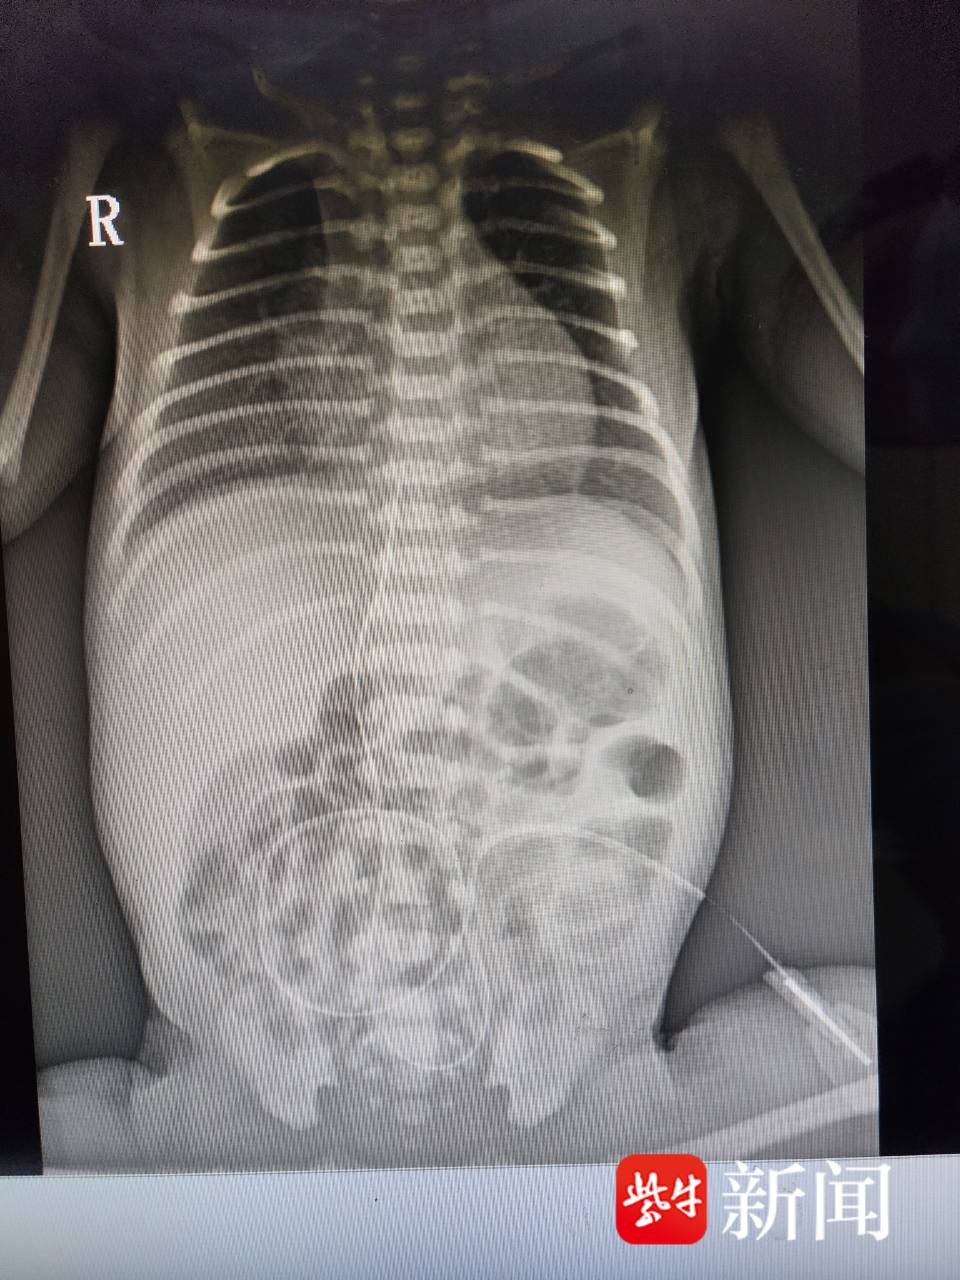

在征得患儿家长同意及充分的术前准备后,治疗团队严格按照脐静脉置管术操作流程,精准实施每个步骤的操作。经床旁摄片显示导管末端位置准确,置管非常成功。术后,经过保暖、吸氧及经脐静脉导管输注营养液和血管活性药物等救治措施后,患儿病情得到明显改善。目前,正在进一步康复中。